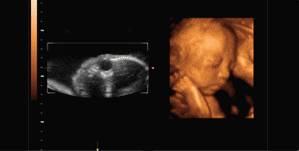

NO.3【三维彩超】

普通B超和彩色B超都是二维平面图像,这两种技术仍在使用,但由于观测效果较为依赖羊水量和胎儿体位,一旦在怀孕晚期羊水减少或者胎儿面向母亲的背部,观测效果就不太理想。

而且,二维图像不能满足准妈妈们"看到"宝宝模样的愿望。

三维彩超就是将二维图像合成模型,透过屏幕可从各个方位观察胎宝宝。

但是,三维彩超虽是立体成像,但图像仍以图片形式观察,观察面为局部,且清晰度稍差于四维彩超。

NO.4【四维彩超】

四维彩超是目前世界上最先进的彩色超声设备,是采用三维超声图像加上时间维度参数,更直观更清晰地呈现胎儿在宫内的动态图像,多方位、多角度地观察胎宝宝的生长发育情况,还能够对孕期潜藏的各类疾病进行精确检测。